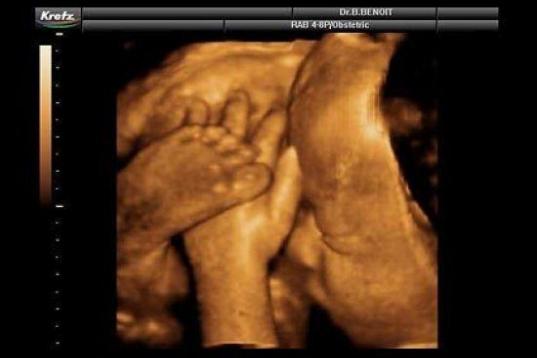

En esta galería puedes ver en fotos como es el desarrollo de un feto de semana en semana:

Desarrollo del feto, en fotos

Ver la galería